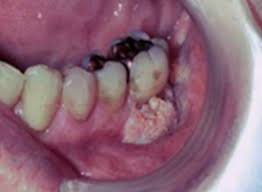

What Does Bone Cancer In The Mouth Look Like - Jaw Cancer Signs Symptoms Causes Diagnosis And Treatment / This can lead to insomnia, loss of appetite, and inability to carry out normal daily activities.. What bone metastasis looks like. Some of the most common oral cancer symptoms and signs include: Inner cheek cancer (also called buccal mucosa cancer) is a type of head and neck cancer that begins when the cells that make up the inner cheek grow out of control and form lesions or tumors. Patches on the lining of the mouth or tongue, usually red or red and white bleeding, pain, or numbness in the mouth mouth ulcers or sores that do not heal Taken by mouth or injection, they attack any cancer cells in the body.

Jaw cancer results in pain in the area with difficulty in opening the mouth. As you review these images and their descriptions, you. Usually it's spotted first by your dentist, so keeping regular dental exams can help with early detection. What bone metastasis looks like. It will show the normal anatomy of the bone and the additional growth arising from the bone and we can see the exact dimensions of the cancer and its local extent of spread and invasion into the surrounding tissues. With time they may spread inside the mouth and on to other areas of the head and neck or other parts of the body. Early on, the pain may only occur at night, or when you are active. Each tumor looks like it's the original site of disease on the scans, suggesting that the bone tumors developed independently, at the same time, at multiple sites. This can lead to insomnia, loss of appetite, and inability to carry out normal daily activities. At first the ulcer is painless, but it later becomes painful. People with a fracture next to or through a bone tumor usually describe sudden severe pain in a bone that had been sore for a few months. Tongue cancer is a type of cancer that starts in the cells of the tongue, and can cause lesions or tumors on your tongue. Cancer in the bones of the spine can press on nerves, causing numbness and tingling or even.

Some of the most common oral cancer symptoms and signs include: Typically, a blood clot forms over your empty socket. Surgery is often the treatment of choice for dog mouth cancer, but it may not lead to a cure because the tumor often has already spread to other parts of the body. Cancer in the jaw often spreads there from other areas of the mouth or throat. Gum cancers may start out looking like a bump or a sore that does not heal. These cells are the most common grounds for mouth cancers. The bone pain is described as aching, throbbing, stabbing, and excruciating. Cancer in bone can cause intermittent or progressively severe localized bone pain where the cancer is in the bone. Treatment for dog mouth cancer. Soft palate cancer starts in the soft palate cells, which are on the upper portion of the back of your mouth, right behind your teeth. Symptoms are similar to more typical osteosarcomas except that they may occur in very young children and are more widespread. One of the most common questions asked by new members in canker sore forums, is what does a canker sore look like? which is understandable as there are many weird things that can happen in your mouth. The accumulating abnormal mouth cancer cells can form a tumor.

Metastatic Tumors To The Jaws A Report Of Eight New Cases from scielo.isciii.es Some of the most common oral cancer symptoms and signs include: Chemotherapy, hormone therapy, and immunotherapy target the main cancer. Other conditions, like osteoporosis or arthritis, may also cause bone or joint pain. Malignant cells in the jaw tend to spread quickly to adjacent organs. The sore may be red or white and may look like a thickening of the gum. At first the ulcer is painless, but it later becomes painful. Soft palate cancer starts in the soft palate cells, which are on the upper portion of the back of your mouth, right behind your teeth. The ulcer may bleed as the cancer grows.

Unlike hard palate cancer, soft. Tongue cancer is a type of cancer that starts in the cells of the tongue, and can cause lesions or tumors on your tongue. Typically, a blood clot forms over your empty socket. People with a fracture next to or through a bone tumor usually describe sudden severe pain in a bone that had been sore for a few months. Treatment for bone cancer in dogs can vary depending on which bones are affected. Abnormal cell growth usually appears as flat patches. A large amount of bone and tissue surrounding the tumor may also have to be removed to eliminate the majority of cancerous cells at the site. Lumps on the roof of your mouth or along your gumline may be the only jaw cancer symptoms you experience. These cancers usually occur in the thin, flat cells called squamous cells that line the buccal mucosa and other parts of the mouth. Gum cancers may start out looking like a bump or a sore that does not heal. Bone cancer can weaken the bone it's in, but most of the time the bones do not fracture (break). It's a type of head and neck cancer. Cancer in the bones of the spine can press on nerves, causing numbness and tingling or even.